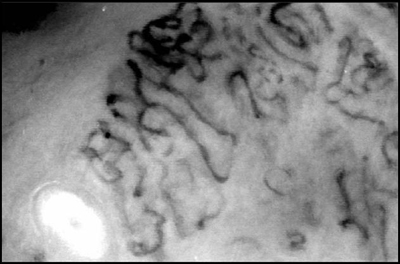

Στην εικόνα 1 βλέπουμε διατομή φλεβιδίου με χρώση Van-Gieson, διακρίνονται οι

ελαστικές ίνες (μαύρες), οι κολλαγόνες ίνες (κόκκινες) και οι λείες μυικές ίνες

(χρωματισμένες κίτρινες).